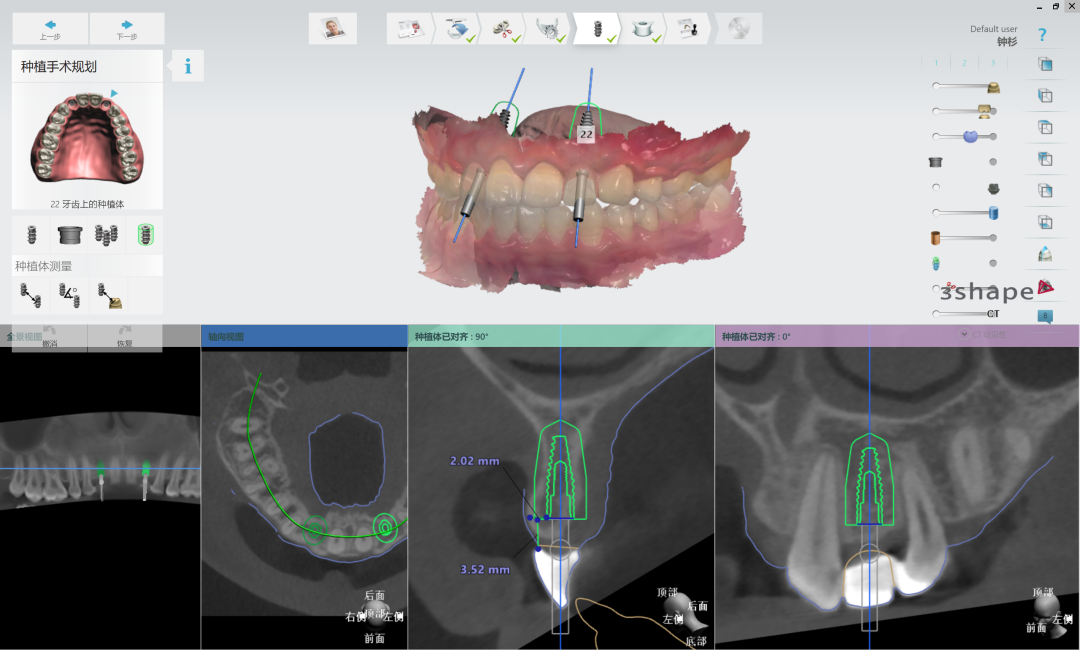

根据最终的美学蜡型效果进行椅旁种植导板设计

根据种植体位置,设计带翼预成临时冠

15分钟快速打印种植导板

椅旁快速打印预成临时冠